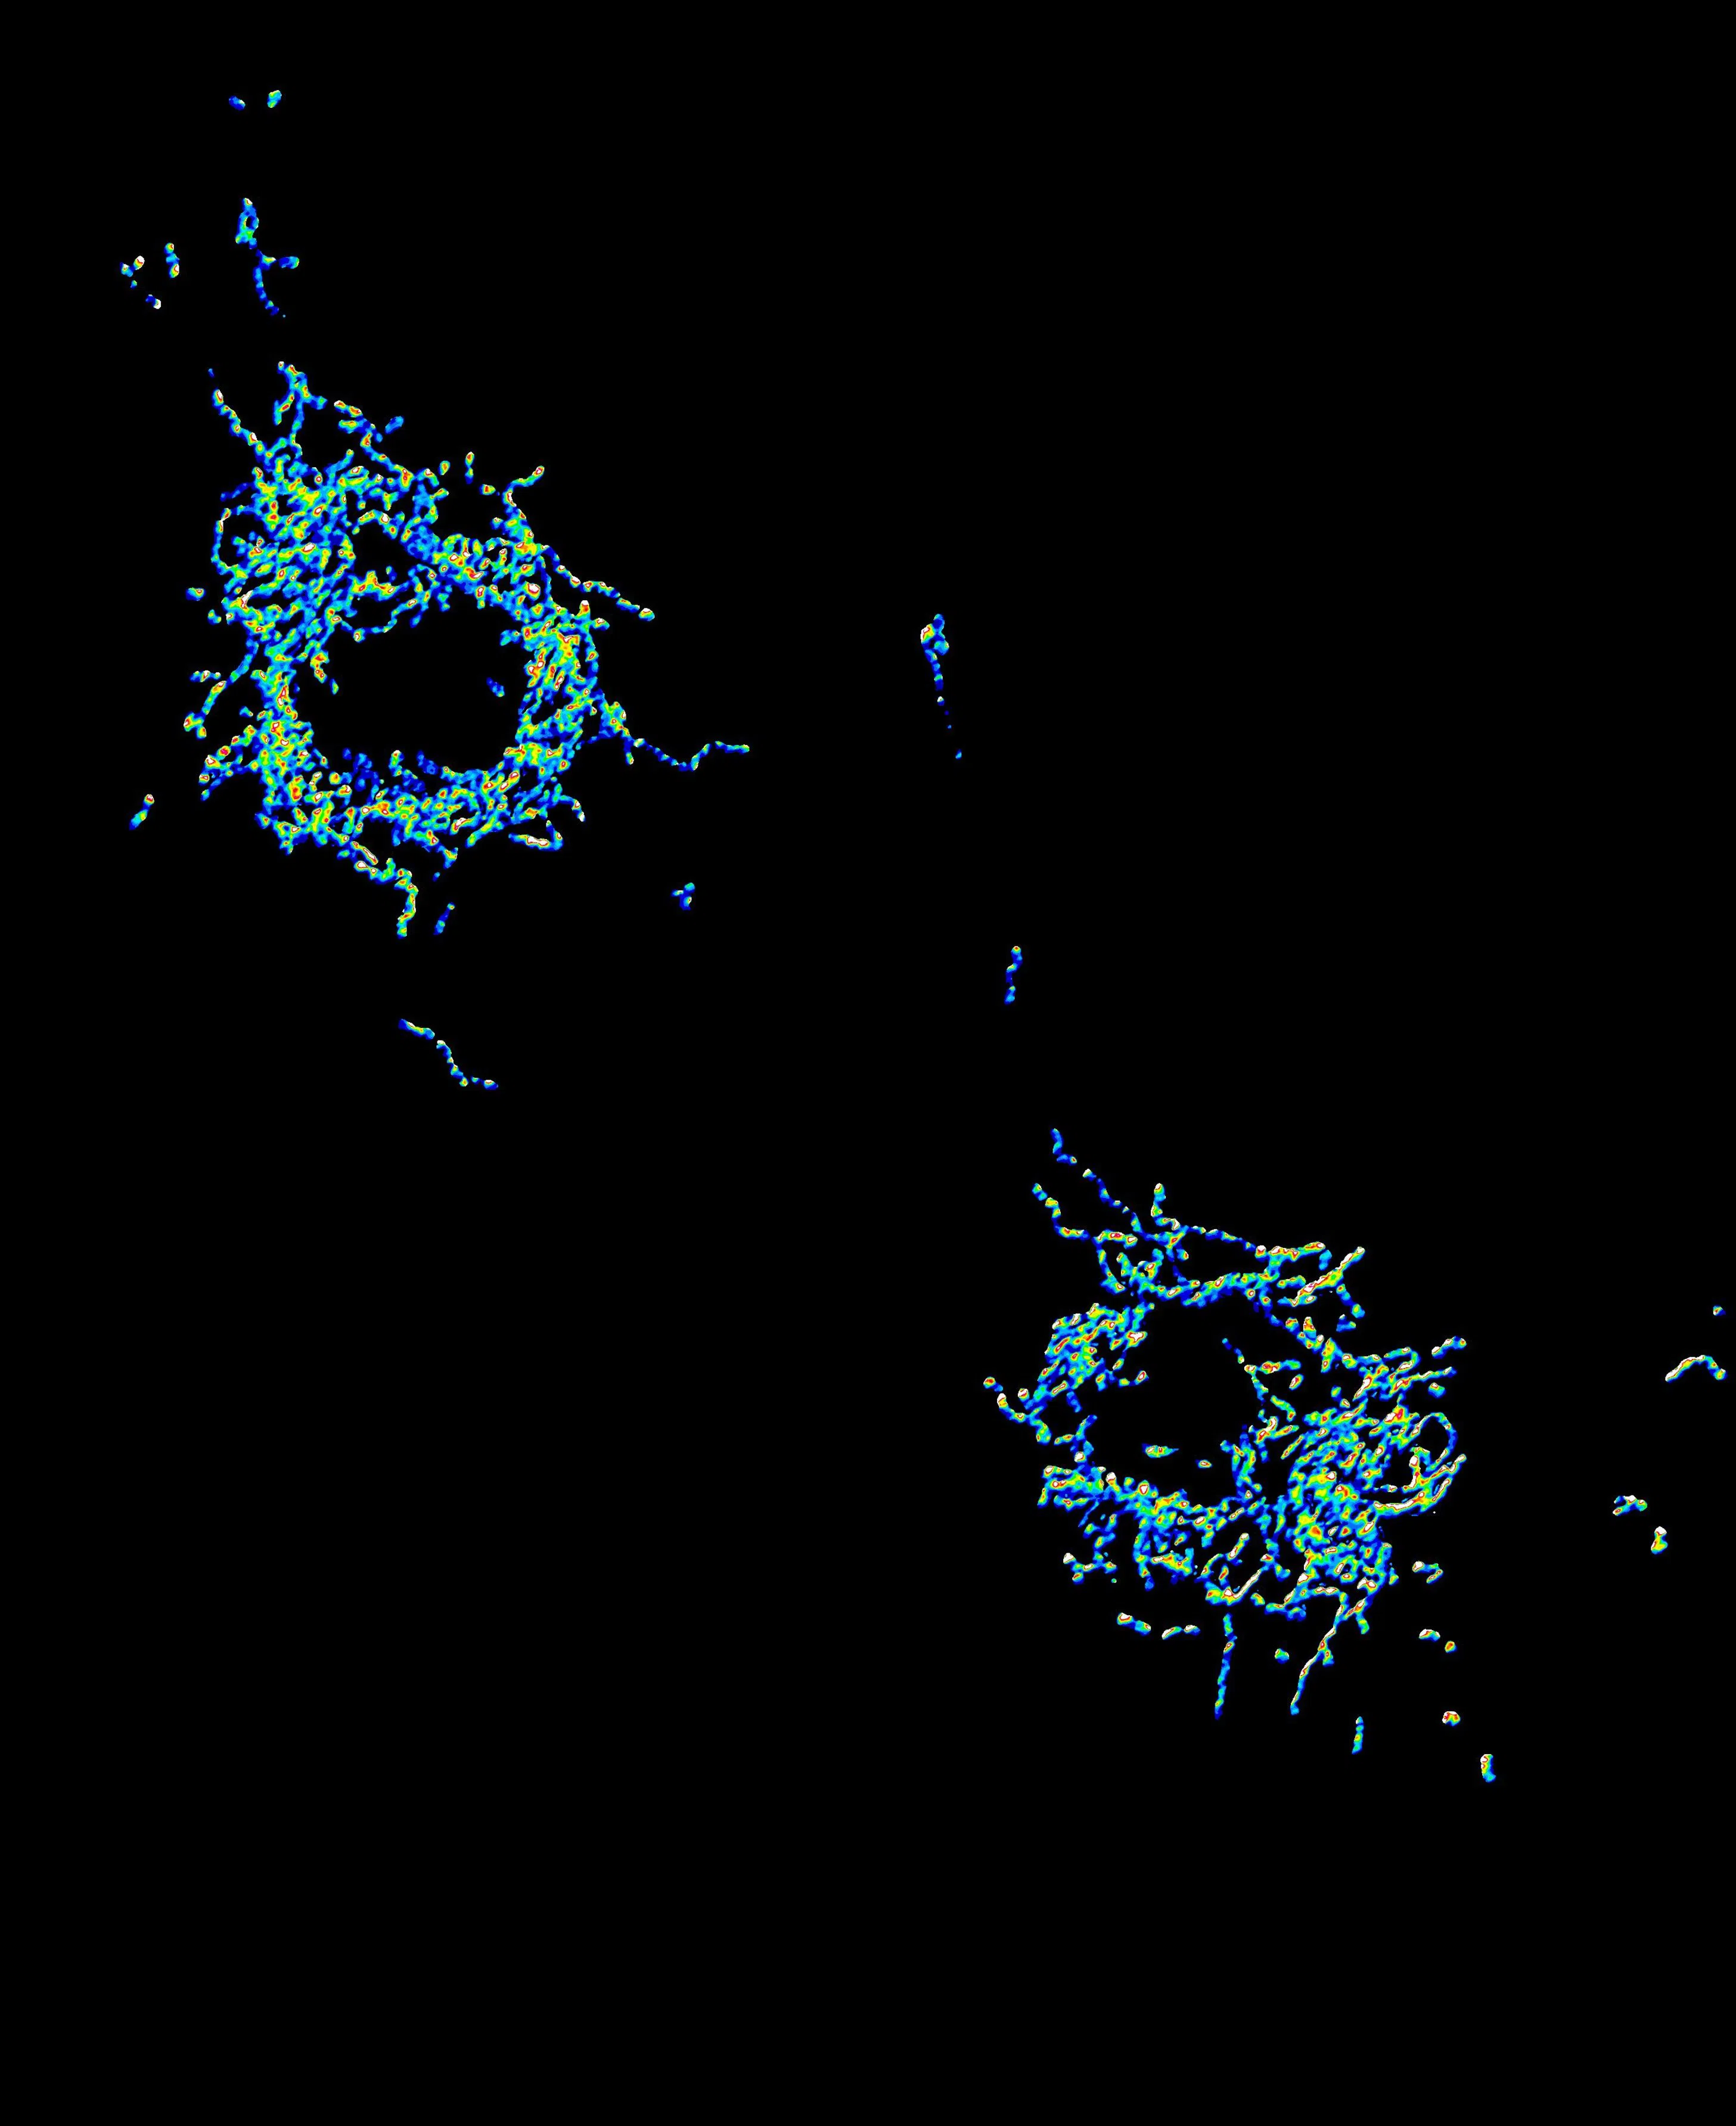

An image showing the enzyme hexokinase-2 stuck all over the mitochondria of brain immune cells called microglia. Mitochondria are the power stations of cells.

PHOTO: NTU